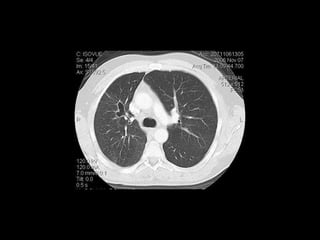

ASPERGILOSIS CRÓNICA NECROTIZANTE

• Necrosis e inflamación granulomatosa.

• DM, malnutrición, alcoholismo, uso crónico de

corticoesteroides y EPOC.

• Tos crónica, esputo, fiebre y síntomas constitucionales.

ASPERGILOSIS CRÓNICA NECROTIZANTE •Necrosis e inflamación granulomatosa. • DM, malnutrición, alcoholismo, uso crónico de corticoesteroides y EPOC. • Tos crónica, esputo, fiebre y síntomas constitucionales. Spectrum of Pulmonary Aspergillosis: Histologic, Clinical, and Radiologic Findings Tomás Franquet, Nestor L. Müller, Ana Giménez, Pedro Guembe, Jesus de la Torre, and S. Bagué RadioGraphics 2001 21:4, 825-837

Spectrum of PulmonaryAspergillosis: Histologic, Clinical, and Radiologic Findings Tomás Franquet, Nestor L. Müller, Ana Giménez, Pedro Guembe, Jesus de la Torre, and S. Bagué RadioGraphics 2001 21:4, 825-837